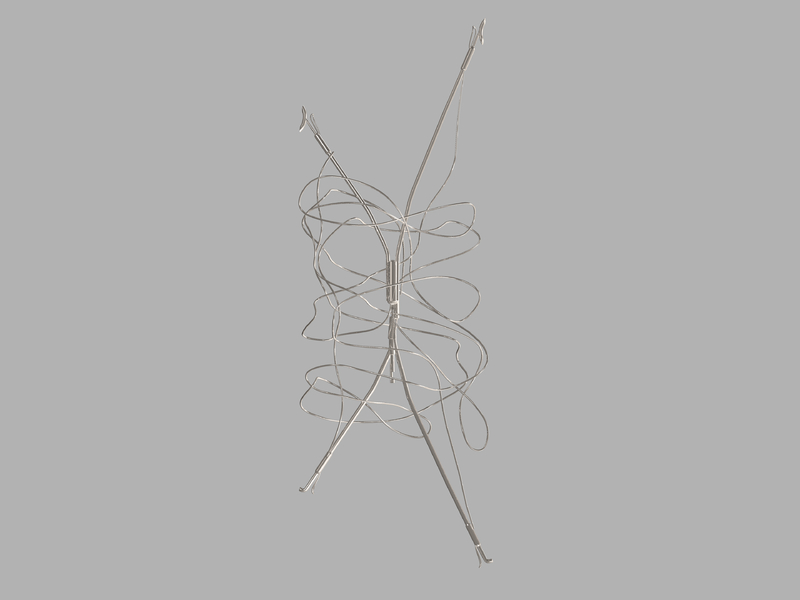

Device-Type

Vena Cava Filter

The Bird's Nest Vena Cava Filter set consists of

- 11 French filter catheter, 45 cm long, with preloaded stainless steel filter and wire guide pusher

The Stainless steel filter is introduced and placed in the inferior vena cava utilizing standard percutaneous entry ( Seldinger) technique.